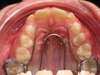

Après expansion

Quadhélix en place : invisible